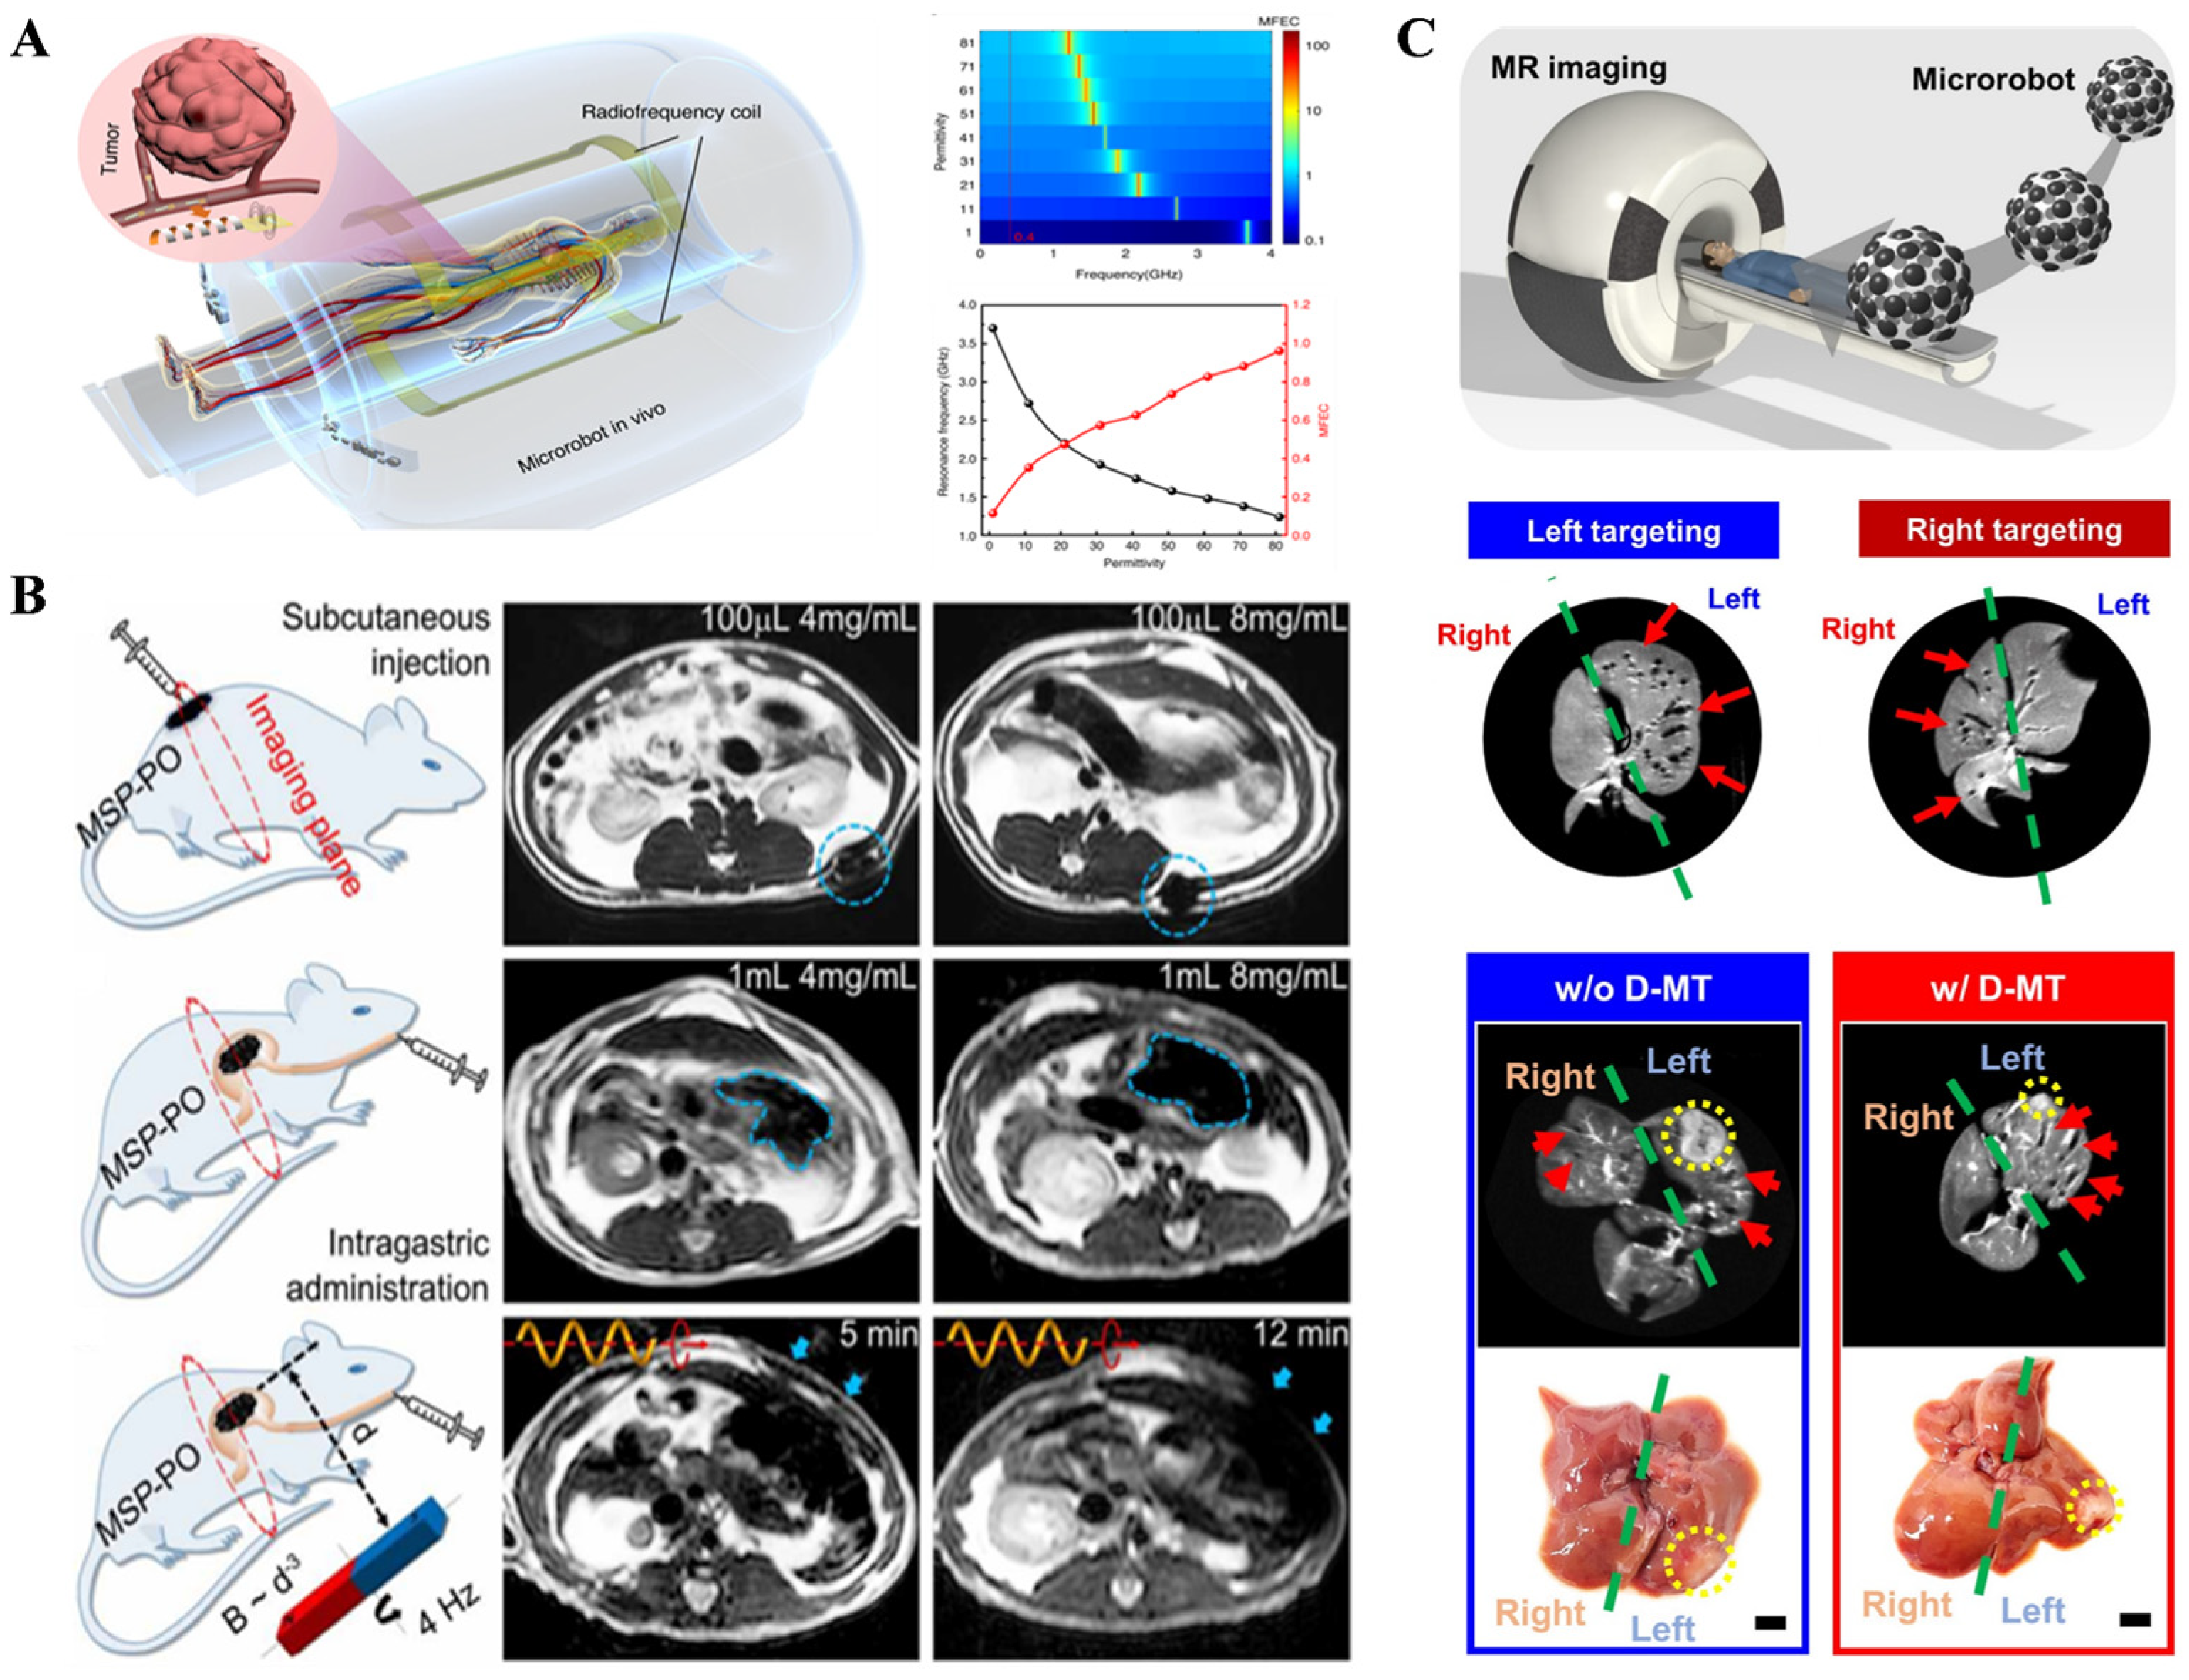

2.2. Magnetic Field-Assisted Imaging Techniques

2.2.1. Magnetic Resonance Imaging (MRI)

2.2.2. Magnetic Particle Imaging (MPI)